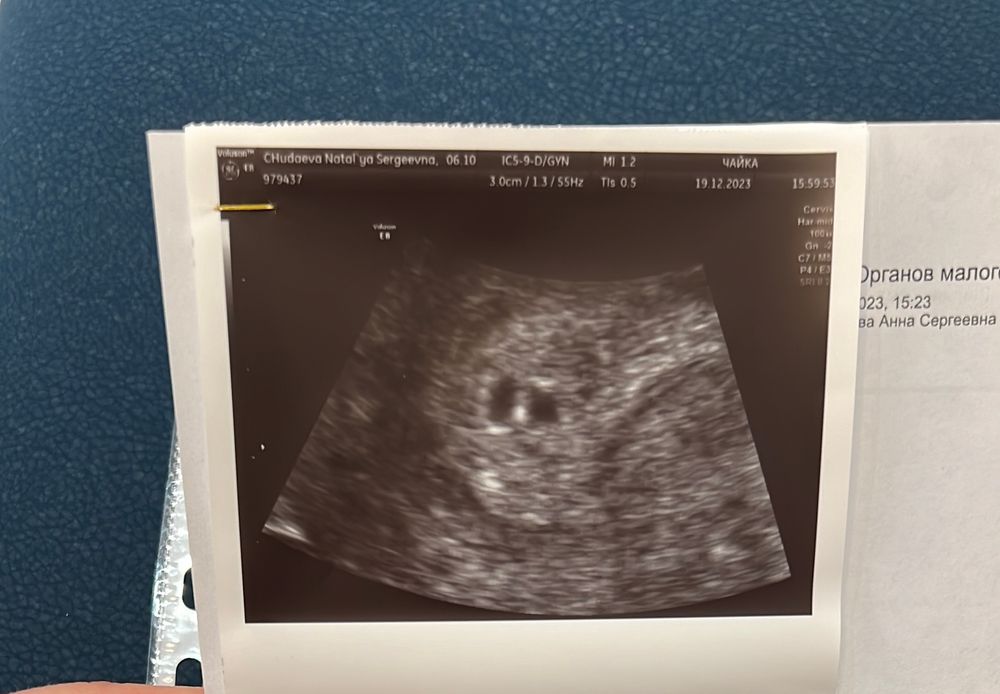

УЗИ на 18 дпп

Похоже не 2 плодных яйца 🧐

Это 2 плодных яйца

Анастасия, хотя мне уши и сказала что овальное слева не похоже на плодное яйцо и если бы разделились они как то по другому бы выглядели, ну вот ещё 22 на узи пойду🙏🏼

А что за реакция эндометрия? На имплантацию? Или как вам объяснили? Просто у меня по узи при подсадке 1 эмбриона, тоже рядом ещё образование чуть меньше. Узист сказала пока непонятно что это

Ольга, просто сказала реакция эндометрия на беременность и всё😅 сказала может и второе плодное яйцо но она не уверенна